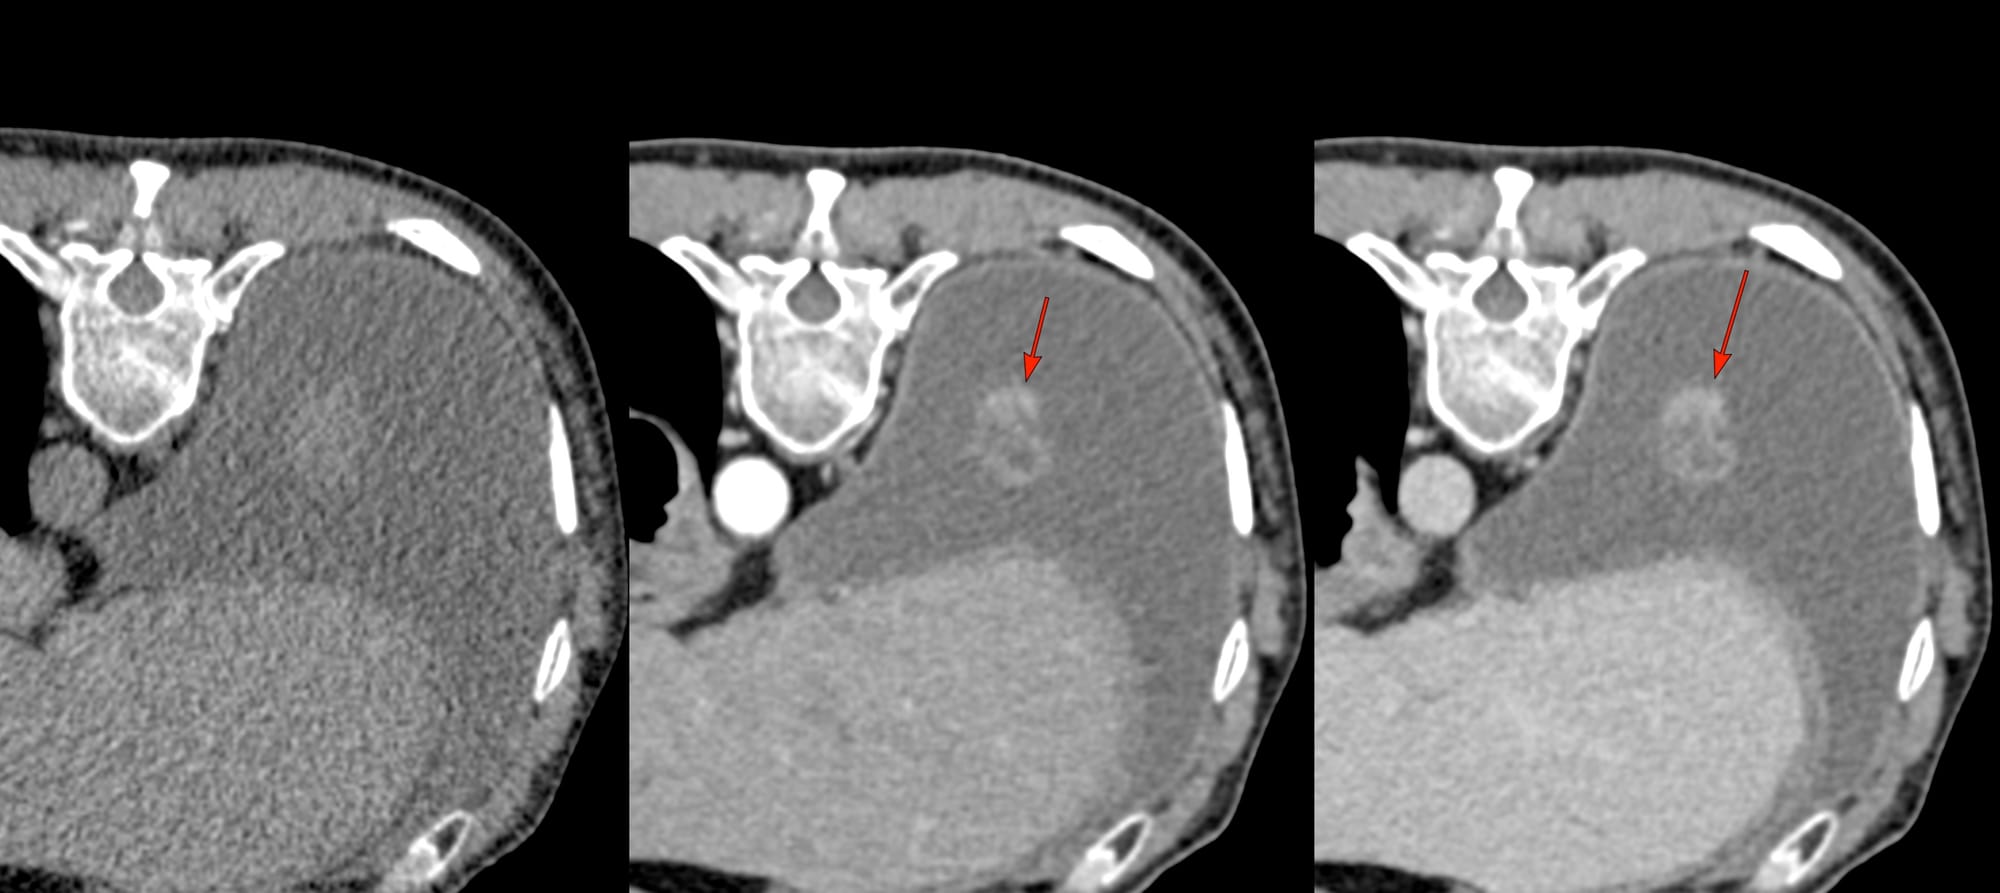

PET/CT showed a focal lesion arising from the posterior basal segment of the right lower lobe attached to the visceral pleura (arrows in Fig 1).

The patient was referred for a CT guided biopsy.